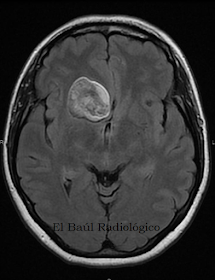

Atendiendo a su composición histológica y bioquímica, los quistes dermoides están formados por una cápsula gruesa de epitelio escamoso. En su interior se acumula un fluido viscoso, formado por material lipídico procedente de la queratina y de la secreción (sebo) de las glándulas sebáceas. No hay tejido adiposo (grasa) en el interior de estos quistes aunque los coeficientes de atenuación, medidos en las exploraciones de TC, sean parecidos a los de la grasa. Hay que tener en cuenta que la grasa es un lípido, pero no todos los lípidos son grasas, como sucede en este caso. En algunos quistes pueden encontrarse ovillos de pelo en su interior, derivados de los folículos pilosos. Conociendo la composición del quiste dermoide y la diferencia que existe con el epidermoide o los lipomas se pueden interpretar mejor los hallazgos que se descubren en las imágenes de TC e IRM. El protocolo de "rutina" se queda siempre incompleto con este tipo de lesiones.

FIGURA 3-G) Imagen FSE-T1. Masa hiperintensa con alto contenido lipídico, con trazos oscuros curvilíneos en sus interior, que pueden corresponder a ovillos de macromoléculas proteicas.

FIGURA 3-I) Imagen FLAIR-T2. Aspecto heterogéneo del quiste dermoide.

FIGURA 3-J) Imagen FSE-dP. Aspecto heterogéneo del quiste dermoide.

FIGURA 5-D) Imagen FSE-T1. Masa hiperintensa, heterogénea, con alto contenido lipídico. Con los hallazgos de la TC previa el diagnóstico de quiste dermoide es casi la única opción. Los quistes epidermoides puros, no suelen brillar en la potenciación en T1 salvo que estén complicados y hayan sangrado.